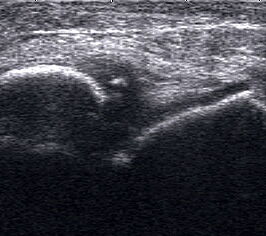

Ganglien imponieren als runde, echofreie Raumforderungen.

Abbildung 9

Lagerung: Rückenlage.

Schnittebene: LS und TS über der Pathologie.

Referenzstrukturen: Reproduzierbare knöcherne Landmarken in Abhängigkeit von der Lokalisation. Befunde: Ganglien finden sich häufig im fibularen Anteil der Gelenkkapsel des oberen Sprunggelenks (Abb. 9), aber auch an den Gelenkspalten und paratendinös im Bereich von Sehnenscheiden streck- oder beugeseitig. Ganglien sind sonographisch als meist runde echofreie Raumforderungen gelenk- oder sehnennah darstellbar.